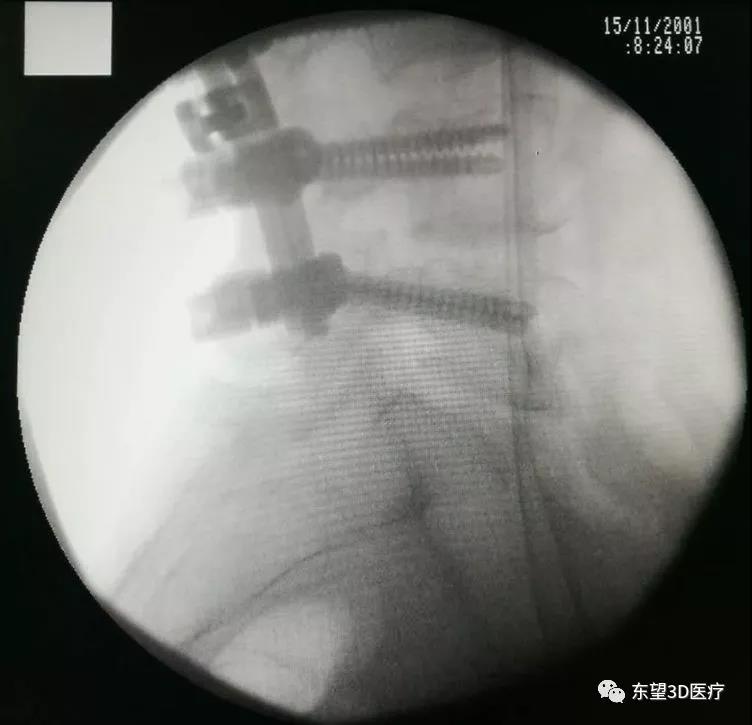

術中腰2椎體經椎弓根截骨(PSO),腰1-3椎體間融合,胸10-12腰3-5后柱融合

\

透視見畸形矯正滿意,縫合切口